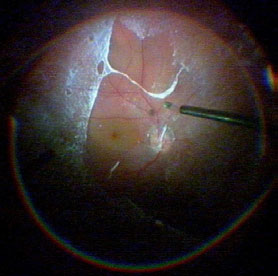

Кроме того, существует ряд интраоперационных наблюдений, когда после витрэктомии на фоне уже произошедшей задней отслойки СТ на поверхности сетчатки всё так же регистрируется «резидуальное СТ» (~~~~~~~~~рис. 5). В таких случаях некоторые хирурги интерпретируют интраоперационную находку как эпиретинальную мембрану. Между тем обнаруживаемый слой можно отнести к нормальному эпиретинальному СТ.

Рис. 5. Интраоперационное фото. После субтотальной витрэктомии с предварительным аспирационно-тракционным отделением кортикального стекловидного тела (СТ) на поверхности сетчатки остался тонкий слой СТ, обнаруженный контрастированием суспензией глюкокортикоида. Часть эпиретинального СТ отделена от поверхности сетчатки. Отчётливо видна граница удалённого с поверхности сетчатки эпиретинального СТ